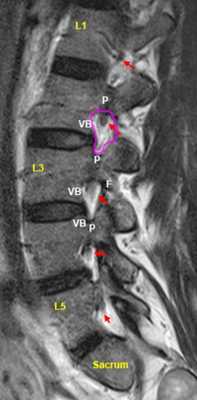

МРТ позвоночника. Т2-взвешенная МРТ, срез через межпозвоночное отверстие. Красные стрелки - корешки. Межпозвоночное отверстие обведено малиновым. P- ножка дуги. VB - тело позвонка.

После того, как появилась ясность в способе получения МРТ изображений позвоночника, надо понять какие анатомические структуры видны. Счет позвонков ведется разными способами - сверху от зубовидного отростка С2 (осевой позвонок), от бифуркации трахеи Т5 ( пятый грудной, с погрешностью на 1 позвонок) или снизу от L5 (последний поясничный), также не исключена погрешность на 1 позвонок в связи люмбализацией или сакрализацией. Анатомия позвоночника в МРТ изображении представлена в нашей другой статье. На серии сагиттальных Т2-взвешенных МРТ позвоночника видны асе основные структуры, причем удается проследить ход корешков конского хвоста. В поясничном отделе он идет под углом вниз и выходит через межпозвоночное отверстие нижележащего позвонка. Аксиальные (поперечные) МРТ срезы всегда делаются вдоль межпозвоночного диска, то есть с учетом нормальных или патологических изгибов позвоночника. Они наиболее удобны для оценки состояния дугоотростчатых суставов. При МРТ позвоночника в поперечной плоскости МРТ срезы часто делают на разных уровнях для лучшей визуализации состояния корешков по их ходу - в дуральном мешке, затем боковом кармане дурального мешка, далее в межпозвоночном отверстии и, наконец, после выхода из него. Таким образом, в поперечном МРТ срезе позвоночника через межпозвоночное отверстие на поясничном уровне можно видеть отрезки сразу двух корешков - вышележащего на выходе из отверстия, и нижележащего в боковом кармане.